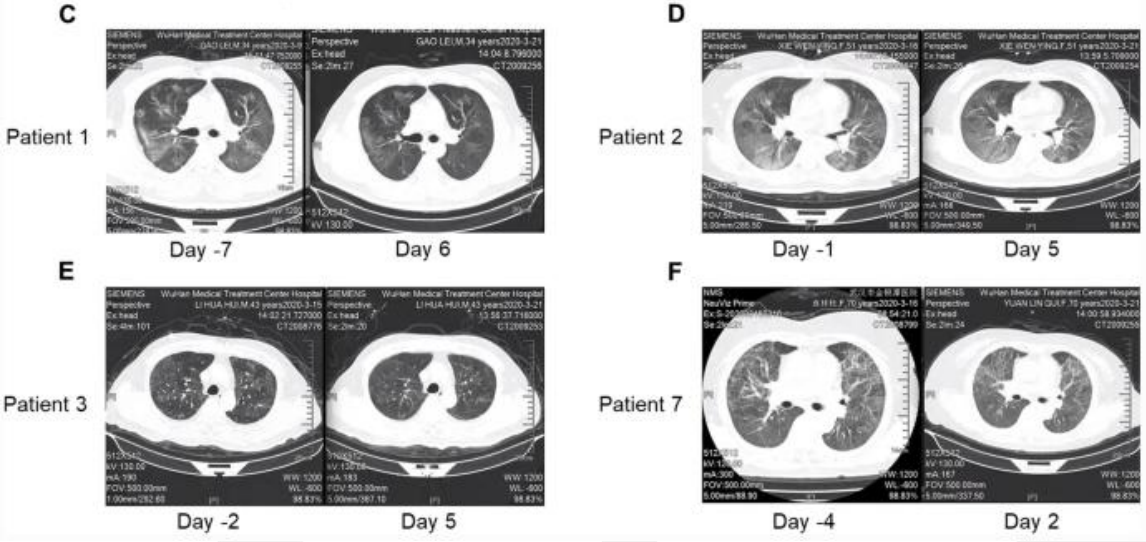

在炎症方面,觀察到(dào)下(xià)降趨勢,包括6↓✔✘人(rén)出現(xiàn)C反應蛋白(bái)下(xià)降、5人(rén€¥€λ)白(bái)細胞介素6(IL-6)下(xià)降,6個(gè)乳酸脫氫酶(LDH)減少(s∑♣hǎo)。7名患者的(de)CT評分(fēn)值在氣霧劑治療後均下(xià)降(☆∏見(jiàn)下(xià)圖E-K)。

所有(yǒu)患者在氣溶膠吸入haMSC-Exos後肺部病變不(bù)同≥&$←程度的(de)消退,其中一(yī)位70歲女(nǚ)性患者的(de)肺部影€λ✘α(yǐng)像改善最為(wèi)明(míng)顯,也(yě)有(yǒu)患者出現(xiàn)£₹∑浸潤和(hé)磨玻璃影(yǐng)消失(見(jiàn)下(xià)圖)。

▲患者吸入haMSC-Exos前後胸部 CT 掃描的(de)變化(huà)